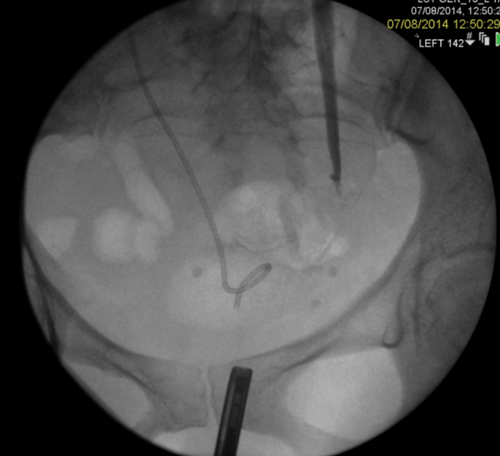

3a. Right antegrade wire insertion and pull-through.

3b. Right JJ stent in situ. Failed left antegrade wire passage.

3c. Left intraoperative nephrostogram showing obliterated left distal ureter.

3d. Right nephrostogram one week postoperative.

Figure 3: A 51-year-old woman, initially presenting with acute kidney injury, with bilateral distal ureteric obstruction secondary to locally advanced cervical cancer. Bilateral rendezvous, technically successful on right but failed on left secondary to ureterovaginal fistula.